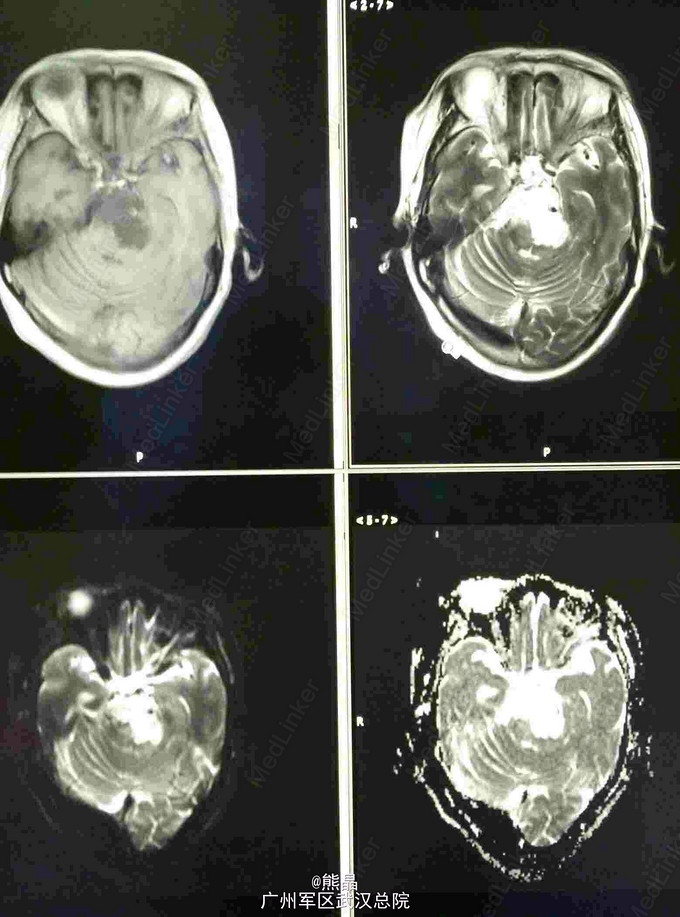

查体:左上肢屈曲状态,不能伸直 CT:碟鞍区及脑干区可见大片状密度减低影,右侧碟鞍骨质有破坏征象 MRI:肿块呈长T1长T2信号,增强呈蜂窝状强化